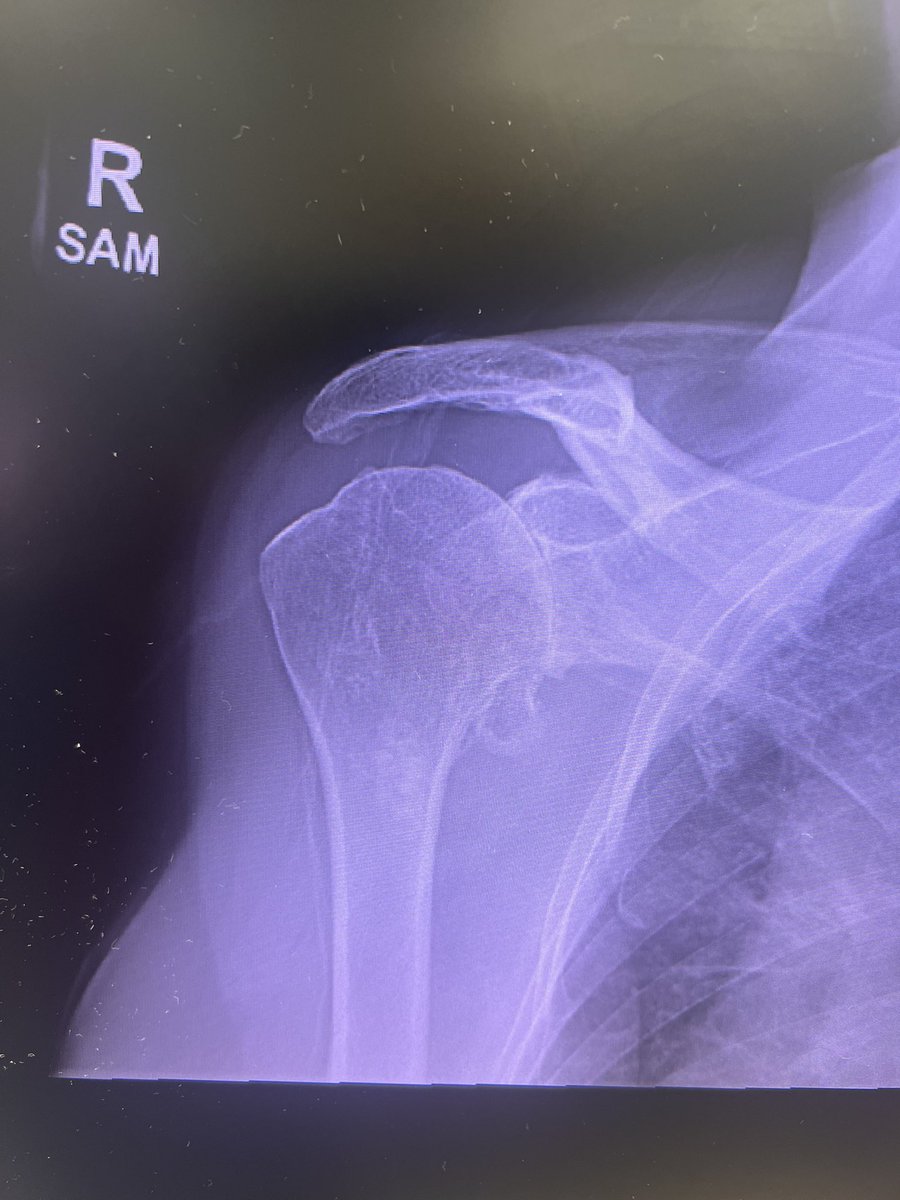

Incredibly excited to officially start my practice as a Shoulder and Elbow Surgeon at @DMC_Heals! Looking forward to seeing patients in Detroit, Dearborn, and Warren.

Orthopaedic Shoulder & Elbow Surgeon at Detroit Medical Center (Detroit, Dearborn, Sterling Heights). Team Physician for Detroit City FC. Opinions are my own.